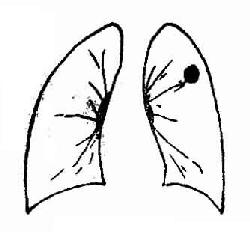

2.周围型肺癌(图3-31)又称肺野型,系指发生于肺段以下支气管直到细小支气管的肺癌。临床症状出现较晚。

周围型肺癌

图 3-31 周围型肺癌

X线表现:早期肿块较小,直径多在2cm以下,显示为密度较低、轮廓模糊的阴影,平片与炎症相似;但断层摄影可显示为球形致密影,轮廓较为清楚,边缘毛糙,有短毛刺。

癌肿继续发展,成为3cm以上较大的球形或圆形块影,平片显示密度较高,轮廓清楚,外形多呈分叶状,或有短小毛刺。有时表现为肺炎样小片状浸润,密度可不均匀。

癌瘤发生坏死,与支气管相通经排出后,可显示偏心性不规则空洞,或有结节向洞腔内突出。多数没有液平,如伴有感染可出现明显的液平。

肿块增长速度,和癌细胞的类型有关。癌体直径在3mm以下时平片不能显示。一般肿块直径达2~3cm以后,生长较快,通常在3~6个月期间则有明显增大。未分化小细胞癌生长最快,可在一个月期间就有明显增大,鳞癌的生长较慢。

周围型肺癌须与结核球肺囊肿良性瘤、慢性脓肿等相鉴别。